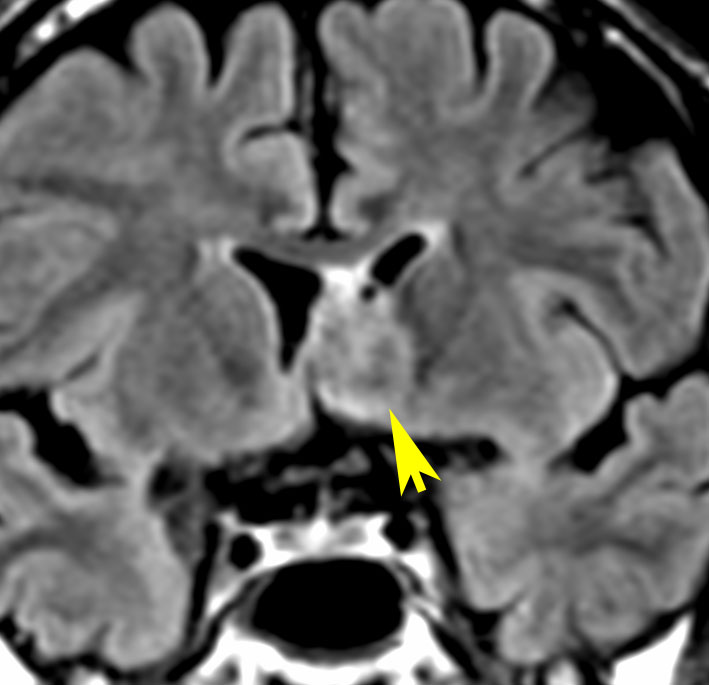

全く何もしなくても良い成人の毛様細胞性星細胞腫

20代女性に偶然発見された視床下部(第3脳室)腫瘍です,T1低信号,T2で高信号,右側のガドリニウム造影では全く増強されません。毛様細胞性星細胞腫と診断できます。眼科での視野検査で視野欠損はありませんでした。生検術もなにもせず経過をみました。

左が初診時,右が5年後のMRI画像です。腫瘍の大きさは全く同じです。このような腫瘍はしばしば経験します。慌てて生検術や開頭手術など計画しないで,画像診断をしっかりすることが大切です。